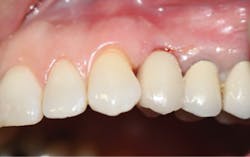

After a three-month integration period, final impressions were taken for a screw-retained crown. The procedure was noneventful, and not only was the patient happy having a provisional tooth, but the relief offered with a permanent fixed solution changed his entire outlook (figures 5 and 6).

Figure 6: Final implant restoration